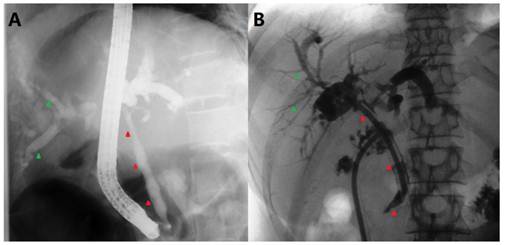

Fig 3

Abdominal CT and MRCP at 2nd admission. A) Arterial phase and B) Venous phase CT scan demonstrating apparently normal intrahepatic and extrahepatic bile ducts (red arrowheads denoting CBD). C) Fast-echo MRI hydrography demonstrating slight dilatation of the intrahepatic bile duct. D) Compared to Fig. 1C, the axial T1-W image shows no clear extrahepatic bile duct thickening.

Unexpectedly, more than 4 years after her original presentation (September 2010), she was re-hospitalized for hyperbilirubinemia. Similar to the first admission, her examination was otherwise normal, and all body fluids were negative for Cryptococcus. The liver function test results from this presentation are listed in Table 1. Radiologic exams at this time revealed a thickened CBD wall, narrow CBD lumen and moderately dilated intrahepatic bile ducts, which were also similar to but slightly less severe than her initial presentation (Fig. 3). Instead of an ERCP, an EUS was performed; it demonstrated a benign change of her CBD entirely from the hilar bifurcation to the duodenal ampulla. A cholangioenterostomy was under deliberation; however, her icterus gradually and spontaneously vanished. By the 14th inpatient day, the patient had recovered and was again discharged. As of the time of this writing, another 16 months of follow-up have passed with no abnormalities detected.